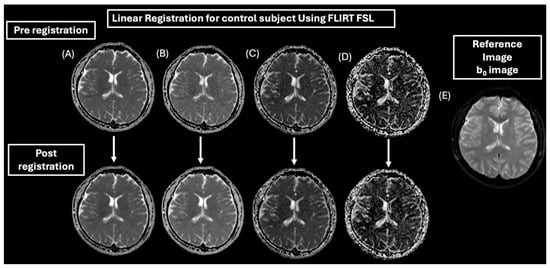

2.4. MRI Processing